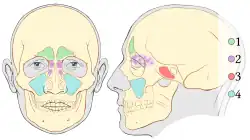

Il existe quatre types de sinus paranasaux :

- Le sinus maxillaire : Le plus sujet à des pathologies. Asymétriques, on trouve un sinus maxillaire droit et un sinus maxillaire gauche. Ils constituent le type le plus volumineux de sinus. Se formant vers 2 ans, son volume va croître considérablement avec le développement de la face, ce qui permet d’alléger le massif facial. Il a une forme de pyramide couchée dont la base répond à la paroi latérale de la cavité nasale et le sommet au processus zygomatique du maxillaire - La face supérieure du sinus maxillaire répond à la face inférieure de la cavité orbitaire - La paroi postérieure est en rapport avec la fosse infra-temporale - Bord inférieur en rapport essentiel avec la région alvéolaire du maxillaire : les racines dentaires ;

- Le sinus frontal : Descend dans les fosses nasales par le canal naso-frontal qui s’abouche à la partie antérieure de la région du hiatus maxillaire. Certains parlent de sinus frontaux (au pluriel) car il est cloisonné avec 2 ou 3 parois orientées dans un plan sagittal ;

- Les sinus ethmoïdaux : Au nombre de 10 à 20, ils sont présents à la naissance. Il ne s'agit pas d'une cavité unique comme les autres sinus mais plusieurs cloisonnements qui forment un labyrinthe au niveau de la masse latérale de l’ethmoïde. On les décrit en 2 parties : cellules ethmoïdales antérieures et postérieures. La partie antérieure des cellules ethmoïdales s’ouvre au niveau du méat nasal moyen et la partie postérieure au niveau du méat nasal supérieur. Les cellules ethmoïdales constituent la paroi médiale de l’orbite ;

- Le sinus sphénoïdal : A l’intérieur du corps du sphénoïde. Rapports : Au-dessus : loge hypophysaire - selle turcique, Latéralement : sinus caverneux, En dessous : les fosses nasales. Il communique avec les fosses nasales par le récessus sphéno-ethmoïdal.